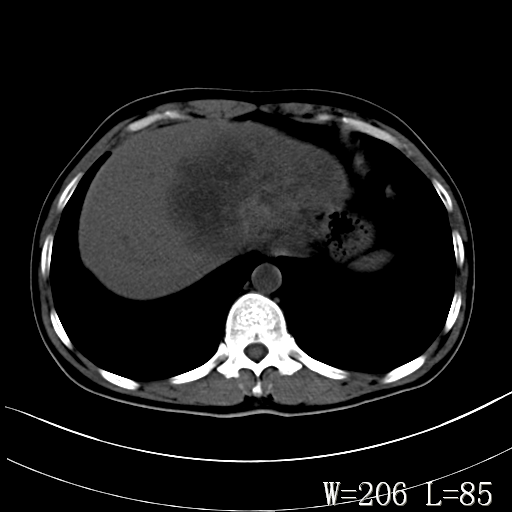

标题: CT27340:肝脏病变? [打印本页]

标题: CT27340:肝脏病变?

男,45岁,发热、乏力半月,午后为主。

对比剂快进快出,首先考虑肝左叶巨块型肝癌。

其次,感染性病变,如肝脓疡不排除。

肝脓肿可能。

蜂巢,肝脓肿

蜂巢状,支持!肝脓肿的诊断。